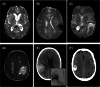

Objective: Determining the underlying causes of intracerebral hemorrhage (ICH) is of major importance, because risk factors, prognosis, and management differ by ICH subtype. We developed a new causal CLASsification system for ICH Subtypes, termed CLAS-ICH, based on recent advances in neuroimaging.

Methods: CLAS-ICH defines 5 ICH subtypes: arteriolosclerosis, cerebral amyloid angiopathy, mixed small vessel disease (SVD), other rare forms of SVD (genetic SVD and others), and secondary causes (macrovascular causes, tumor, and other rare causes). Every patient is scored in each category according to the level of diagnostic evidence: (1) well-defined ICH subtype; (2) possible underlying disease; and (0) no evidence of the disease. We evaluated CLAS-ICH in a derivation cohort of 113 patients with ICH from Massachusetts General Hospital, Boston, USA, and in a derivation cohort of 203 patients from Inselspital, Bern, Switzerland.

Results: In the derivation cohort, a well-defined ICH subtype could be identified in 74 (65.5%) patients, including 24 (21.2%) with arteriolosclerosis, 23 (20.4%) with cerebral amyloid angiopathy, 18 (15.9%) with mixed SVD, and 9 (8.0%) with a secondary cause. One or more possible causes were identified in 42 (37.2%) patients. Interobserver agreement was excellent for each category (kappa value ranging from 0.86 to 1.00). Despite substantial differences in imaging modalities, we obtained similar results in the validation cohort.